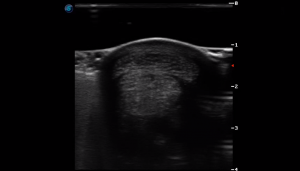

SIMON Ultrasound Database

This ultrasound database is a free resource for students and doctors!

Our collection includes videos of dogs, cats, horses, cows, humans, and many other species!